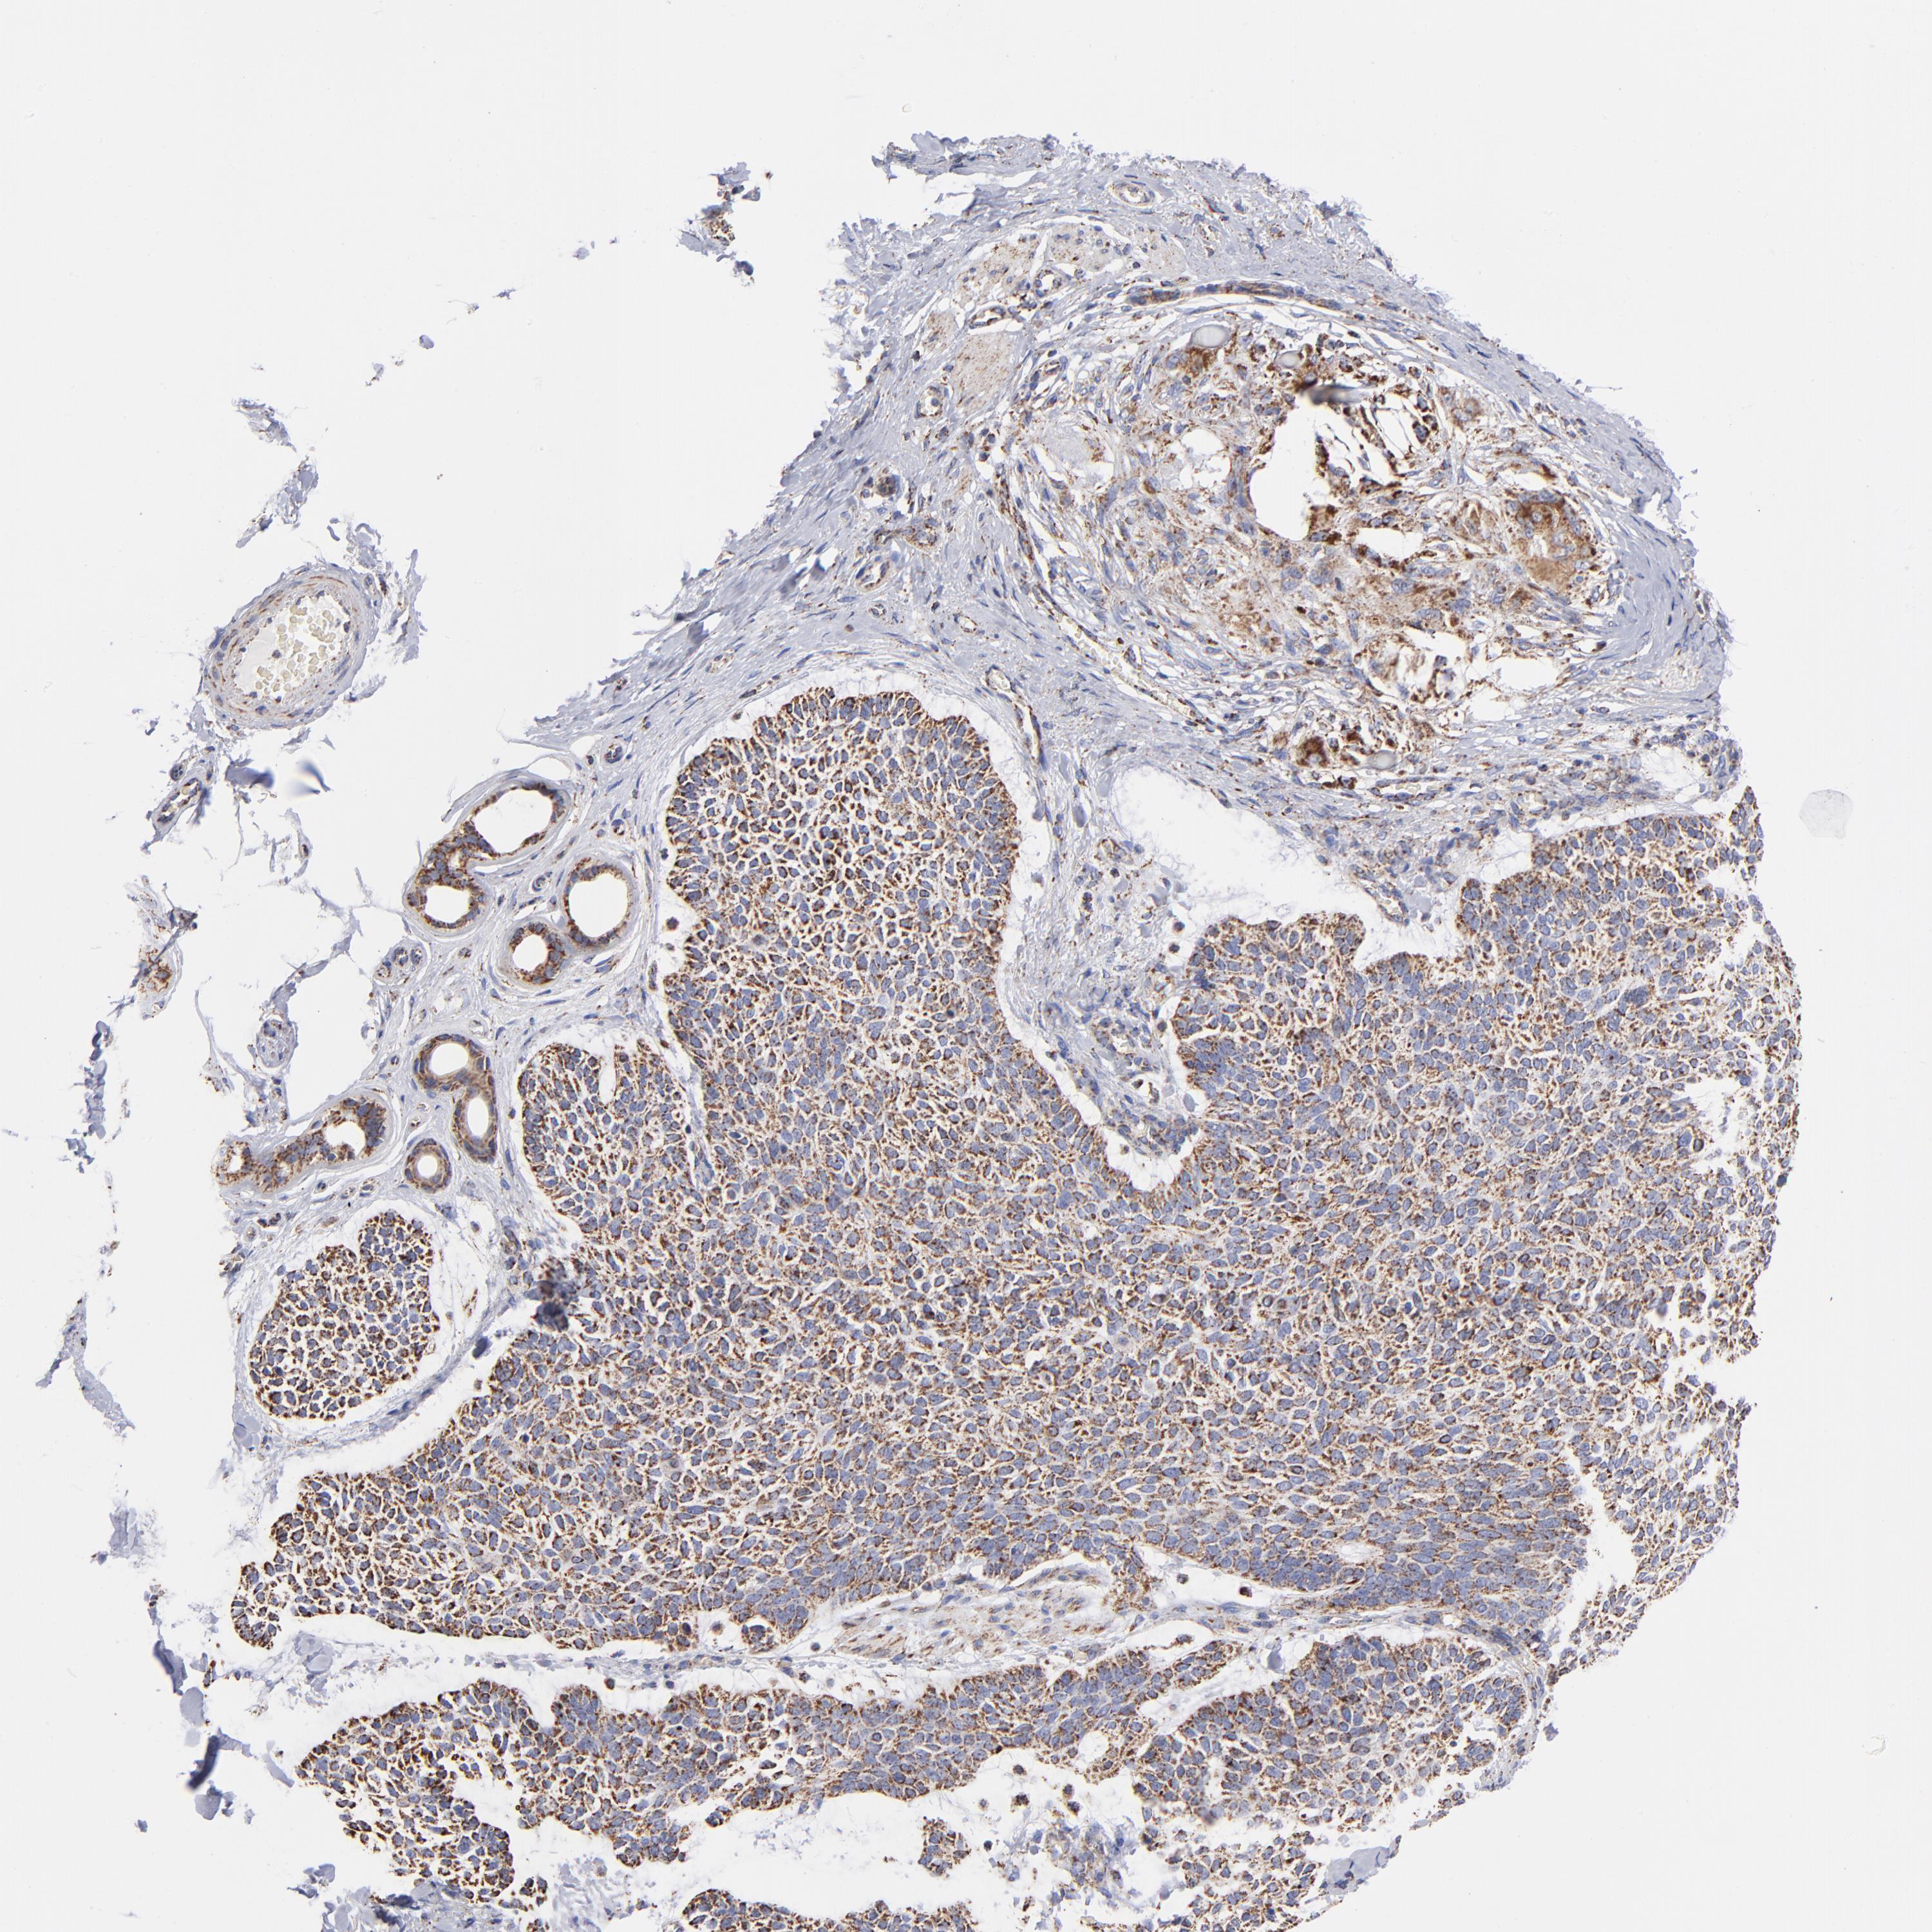

SKIN CANCER - Protein expressioni

A mouse-over function shows sample information and annotation data. Click on an image to view it in a full screen mode. Samples can be filtered based on level of antibody staining by selecting one or several of the following categories: high, medium, low and not detected. The assay and annotation is described here.

Antibody stainingi

Antibody staining in the annotated cell types in the current human tissue is reported as not detected, low, medium, or high, based on conventional immunohistochemistry profiling in selected tissues. This score is based on the combination of the staining intensity and fraction of stained cells.

Each image is clickable and will lead to virtual microscopy that enables deeper exploration of all samples and also displays staining intensity scores, fraction scores and subcellular localization as well as patient and tissue information for each sample.

Antibody HPA003280

Staining

High

Medium

Low

Not detected

Intensity

Strong

Moderate

Weak

Negative

Quantity

>75%

75%-25%

<25%

None

Location

Nuclear

Cytoplasmic/membranous

Cytoplasmic/membranous,nuclear

Squamous cell carcinoma, NOS

Basal cell carcinoma